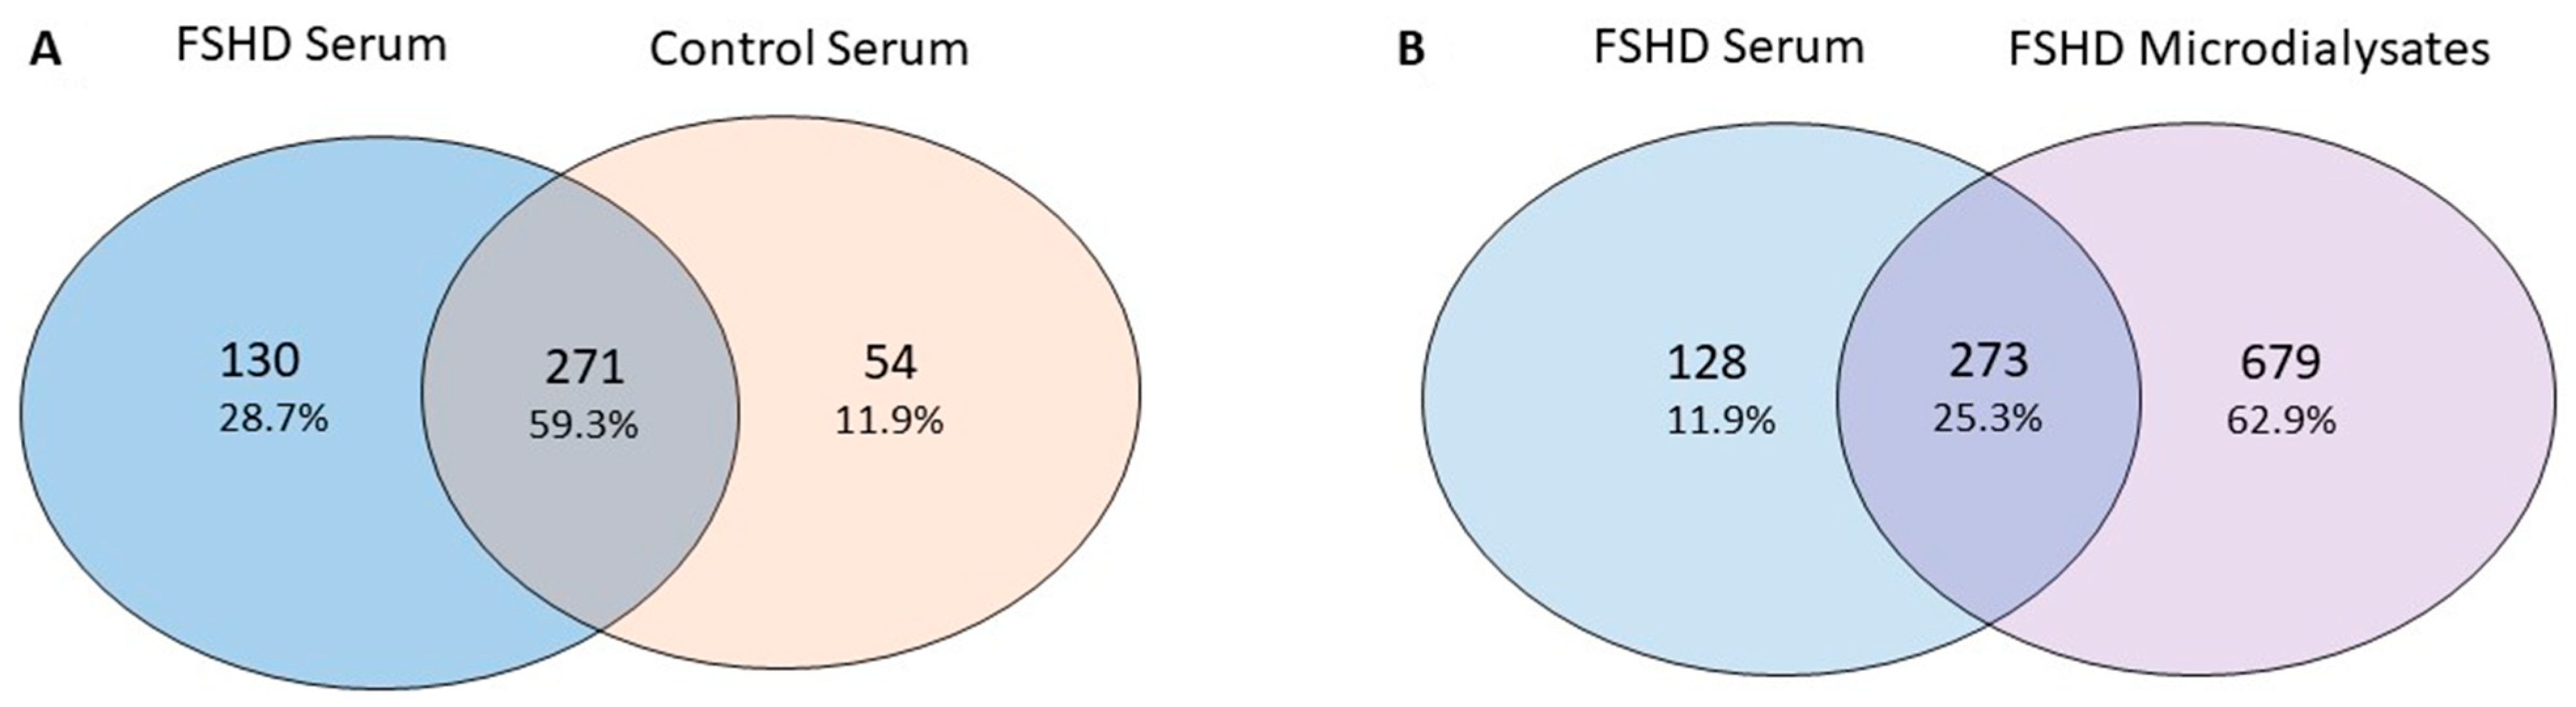

2.7. Serum Analysis